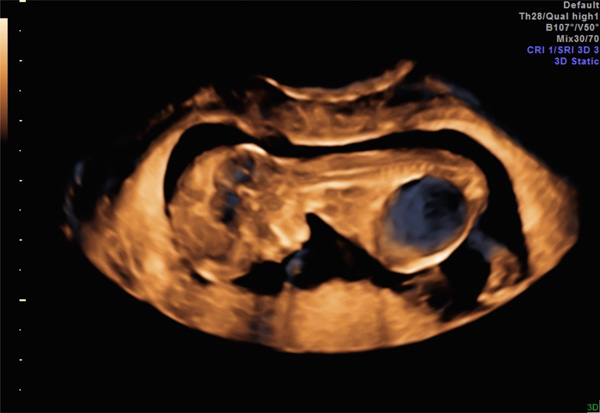

What Causes Enlarged Kidney In Unborn Baby. As i soon learned all too well, hydronephrosis is a condition that involves a backflow of urine in the kidney because of an obstruction. 1) a prenatal ultrasound (ultrasound during pregnancy) may reveal a fetus with dilated kidneys. This keeps the urine from going through to the bladder and out of the body. Many of these kidneys are dysplastic and associated with urinary tract obstruction.

- an ultrasound done as a routine evaluation for another medical problem, such as a urinary tract infection or incontinence, may also reveal hydronephrosis. This is one of he most common things they find at the 20 week scan, the majority of the time it corrects itself after baby is born. A second pattern is the hyperechoic small kidney with abnormal architecture. Sometimes a grape or a bunch of grapes like structure may begin growing inside your unborn baby’s kidneys. Fetal multicystic dysplastic kidney (mcdk) is a condition that affects one or both of your baby’s kidneys before birth. Causes causes for an enlarged kidney.

In some cases, hydronephrosis is mild and goes away on its own without. This keeps the urine from going through to the bladder and out of the body. With ultrasound, the doctor can see the baby�s internal organs, including the kidneys and urinary bladder. Fetal multicystic dysplastic kidney (mcdk) is a condition that affects one or both of your baby’s kidneys before birth. This occurs in 1 per 100 pregnancies.

This condition is often diagnosed before birth during a prenatal ultrasound. Unborn baby & kidney problems. As i soon learned all too well, hydronephrosis is a condition that involves a backflow of urine in the kidney because of an obstruction. In recent years, better ultrasound machines have allowed your doctor to see your baby�s kidneys more clearly during pregnancy. Fetal multicystic dysplastic kidney (mcdk) is a condition that affects one or both of your baby’s kidneys before birth.

During normal development, two thin tubes of muscle called ureters grow into the kidneys and branch out to form a network of tiny structures called tubules. Ultrasound examinations are often done as part of prenatal care. The first is an obstruction of the urine flow in the urethra or kidney. Most commonly, hydronephrosis is found in one kidney. Another finding that causes concern is an enlarged bladder.

What causes kidney problems in unborn babies? The following overview of the urinary tract will help you understand 1) a prenatal ultrasound (ultrasound during pregnancy) may reveal a fetus with dilated kidneys. Fetal multicystic dysplastic kidney (mcdk) is a condition that affects one or both of your baby’s kidneys before birth. Anyone can become affected by hydronephrosis even unborn babies as it can.